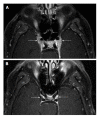

Orbital inflammatory disease (OID) represents a collection of inflammatory conditions affecting the orbit. OID is a diagnosis of exclusion, with the differential diagnosis including infection, systemic inflammatory conditions, and neoplasms, among other conditions. Inflammatory conditions in OID include dacryoadenitis, myositis, cellulitis, optic perineuritis, periscleritis, orbital apicitis, and a focal mass. Sclerosing orbital inflammation is a rare condition with a chronic, indolent course involving dense fibrosis and lymphocytic infiltrate. Previously thought to be along the spectrum of OID, it is now considered a distinct pathologic entity. Imaging plays an important role in elucidating any underlying etiology behind orbital inflammation and is critical for ruling out other conditions prior to a definitive diagnosis of OID. In this review, we will explore the common sites of involvement by OID and discuss differential diagnosis by site and key imaging findings for each condition.